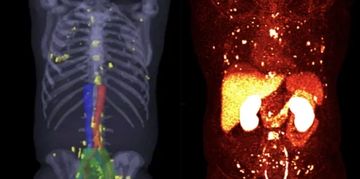

DOTATATE PET

Neuroendocrine tumors, meningiomas, pheochromocytomas

Uses a radioactive tracer targeting somatostatin receptors (SSTR), overexpressed in neuroendocrine tumors.